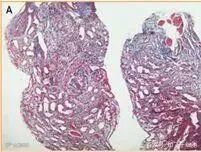

根据文献报道[3],一位73岁的老爷爷被诊断为ANCA相关性血管炎(即系统性血管炎中的小血管炎),而炎症累及器官主要为肾脏。光镜下有8个肾小球上皮呈现新月形,伴有节段性肾小球毛细血管坏死,纤维蛋白破坏,管腔内出现红细胞,间质水肿伴淋巴细胞浸润,见图1。

图1(图片来源参考文献[3])